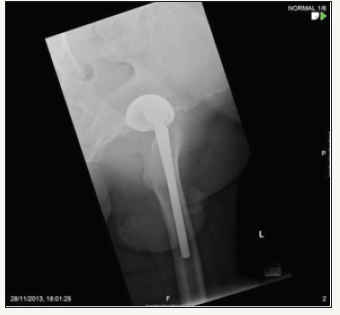

figure 17: Post-op film showing left total hip arthroplasty.

A 73 year old male with Paget’s disease underwent left total hip arthroplasty (Figure 16). A 58mm Pinnacle sector 2 acetabular cup with a neutral Marathon polyethylene liner (28mm IDx58mm OD) was mated via a 28mm+0 stainless steel Elite femoral head (9/10 cone) to a cemented No 3 C-Stem (9/10 taper). Post-op recovery was uneventful. Post-op X-Rays showed 40° inclination of the cup (Figure 17).